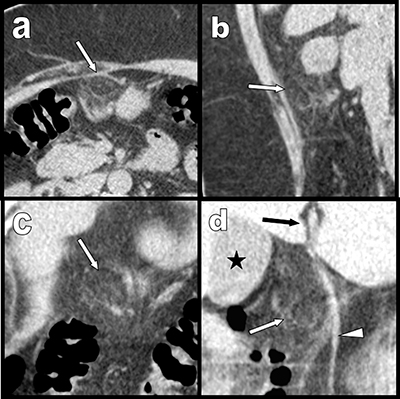

Figure 2

Case 2: similarly to case 1, transverse (a), sagital (b) and coronal oblique (c) and (d) multiplanar reconstructions also show a pre-hepatic area of fat stranding surrounding a 1,5 cm inflammatory lipomatous mass (white arrows) just under the hepatic fissure (black arrow) and in very close vicinity of the ligamentum teres (white arrowheads). Black star = gallbladder. The background noise is more marked than in case one and is related to the obesity of the second patient.